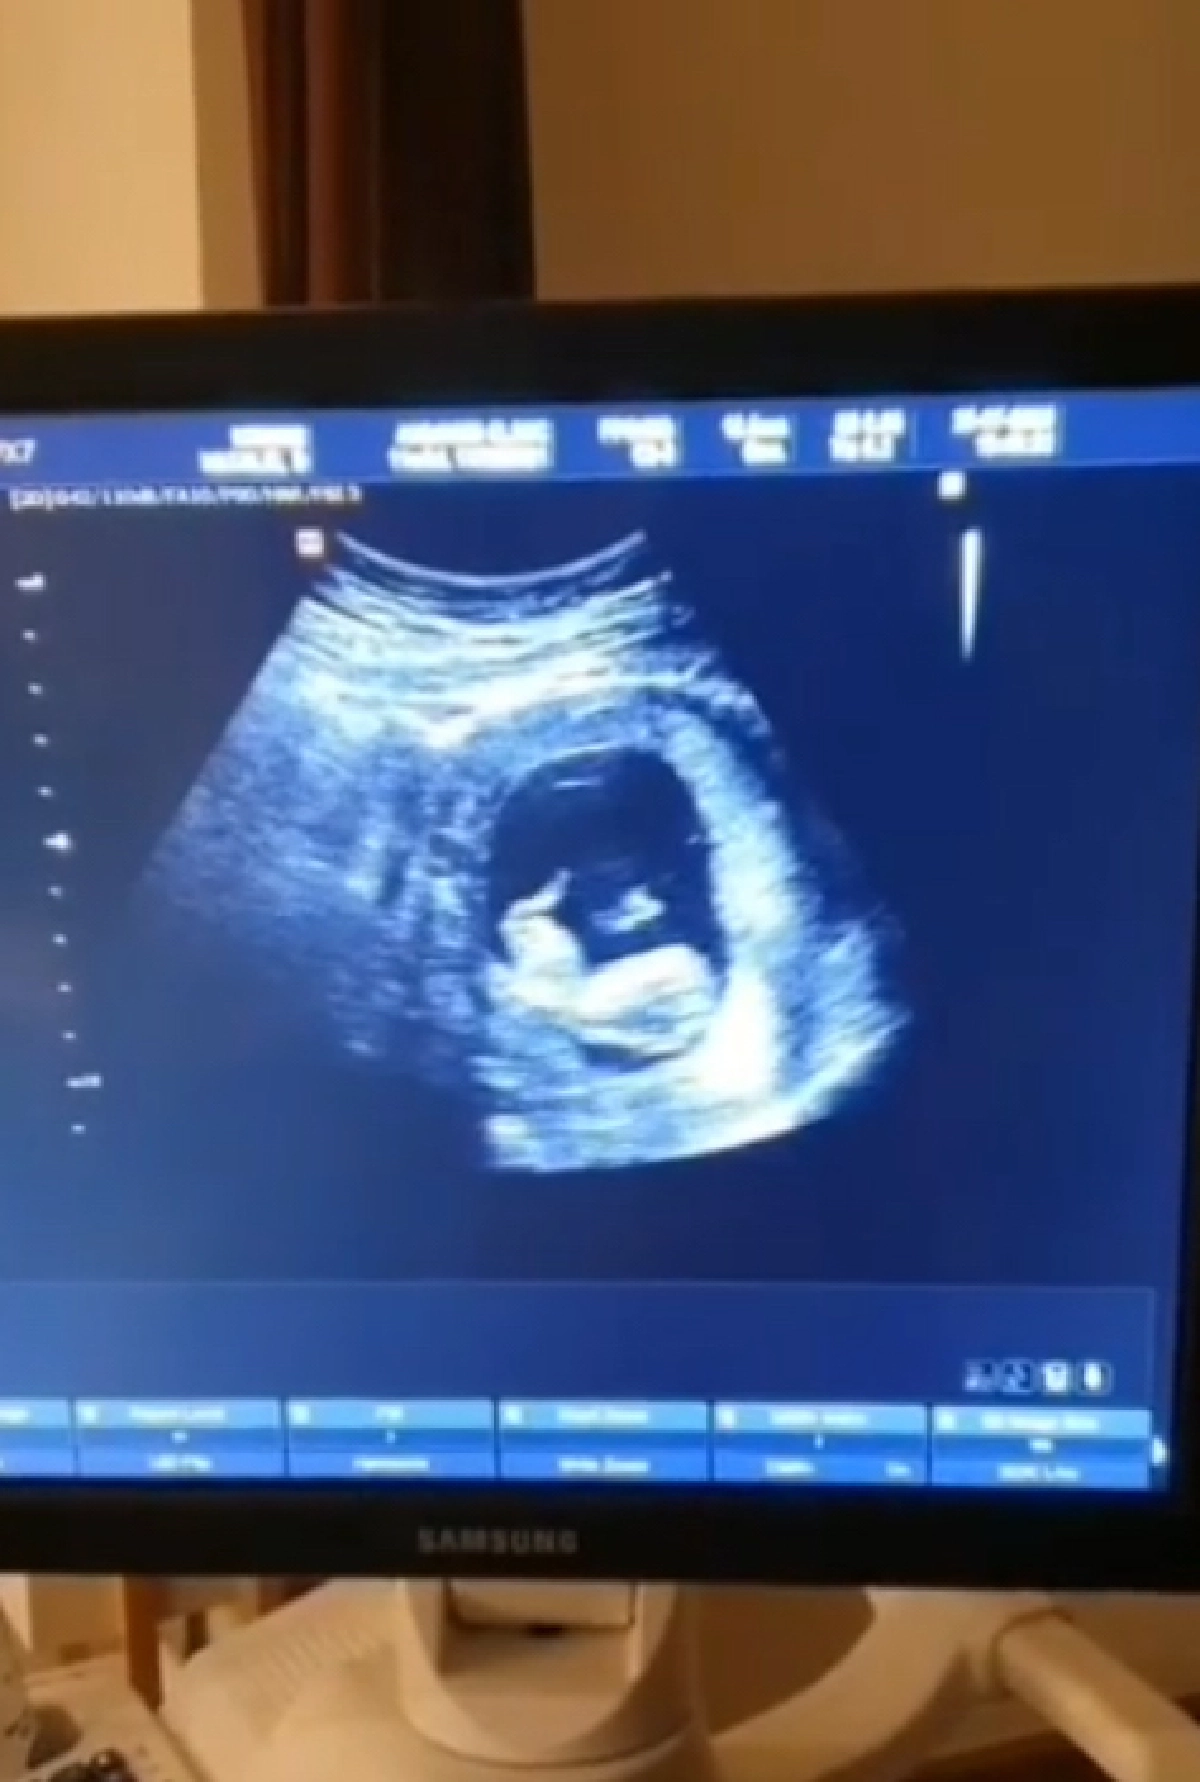

ต้องขอแสดงความยินดีกับว่าที่คุณแม่คุณพ่อป้ายแดง สำหรับอดีตนักร้องสาว “นาตาลี เดวิส” และสามี “ณะ อิทธิกร” ที่ล่าสุดทั้งคู่ได้ออกมาเผยว่ากำลังมีทายาทคนแรกแล้ว พร้อมกับเผยภาพอัลตราซาวด์ลูกน้อยมาให้ได้ชมกัน

โดยทั้งคู่ได้เผยภาพลูกน้อยผ่านอินสตาแกรมส่วนตัวให้ได้ชมกันชัดๆ ซึ่งทางสาว “นาตาลี” ได้เผยอีกว่า "2 คนก็สนุกดี แต่ตอนนี้เรามีลูกชายมาเพิ่มอีกคนแล้ว เย้ ขอบคุณหลาย ๆ คนที่คอยลุ้นคอยถาม ว่าเมื่อไหร่จะมีเบบี๋ ตอนนี้พาเด็กชายมาสวัสดีแล้วคร๊าบบบ #11Weeks1DayPregnant #BabyBoy #งานนี้พ่อทายถูกไป #ยิ้มหน้าบานเล้ยยยย #NtlItk ใน VDO เห็นเจ้าถั่วน้อยเด้งดึ๋ง ๆ ออกมาคงแสบไม่ต้องสืบบบ" งานนี้ก็มีทั้งเพื่อนๆ และแฟนคลับต่างเข้ามาร่วมแสดงความยินดีหับทั้งคู่เป็นจำนวนมาก